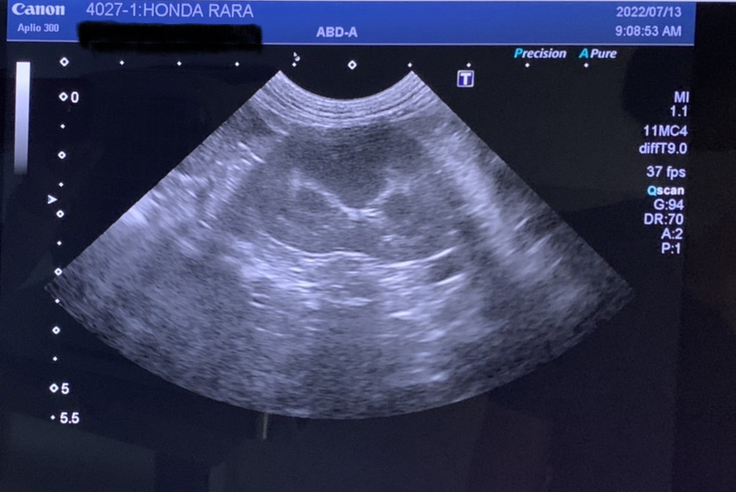

④7/13 定期診察で採血と腹部のエコーをしました。

※病院から掲載許可は得ています。

先生からは、経過は良好。

採血:肝機能は悪くないし、炎症数値も落ち着いているからウイルスは落ち着いている状況。

エコー:お腹に水は溜まっておらず健常の猫とと変わらない状況。

体重:3.46kgで今までと同量の薬💊で良いとのこと。

現状は落ち着いてくれてて本当に良かった・・。ドキドキしながら待つ診察は、ちょっと緊張していました。薬もちゃんと飲めているので一安心。